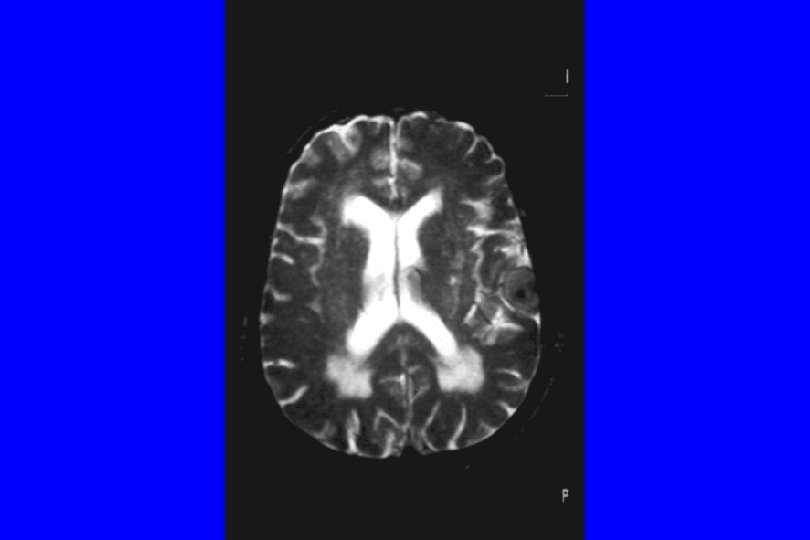

ASPETTI NEURORADIOLOGICI : -La TC Nei soggetti depressi con esordio tardivo, spesso la mostra una dilatazione dei ventricoli. -La RMN di soggetti anziani depressi mostra un'atrofia della corteccia con dilatazione dei solchi corticali e delle scissure silviane e a livello sottocorticale un'iperintensità della sostanza bianca periventricolare (leucoaraiosi), soprattutto nei soggetti con esordio tardivo dei sintomi, una sintomatologia di tipo allucinatorio e una scarsa risposta alla terapia antipertensiva.